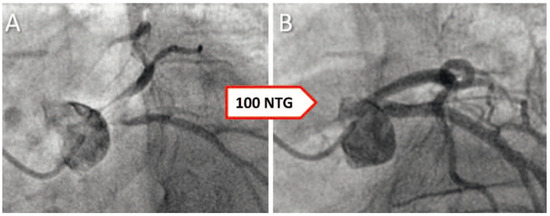

Does Hyperthyroidism Cause Coronary Vasospasms?

We report a 62-year-old women with atypical chest pain who had catheter-induced vasospasms during which she experienced the same type of chest pain she had before hospital admission. In addition, she was found to have hyperthyroidism and was discharged on methamizole and a [...] Read more.

We report a 62-year-old women with atypical chest pain who had catheter-induced vasospasms during which she experienced the same type of chest pain she had before hospital admission. In addition, she was found to have hyperthyroidism and was discharged on methamizole and a beta blocker. Within a few weeks, TSH, fT3, and fT4 normalised, and she did not have recurrent chest pain. Summarising our case report and the existing literature, it appears likely that hyperthyroidism causes coronary vasospasms at least in a subset of patients and therefore, we believe that hyperthyroidism should be ruled out in patients with chest pain that is thought to be secondary to vasospasms. Full article